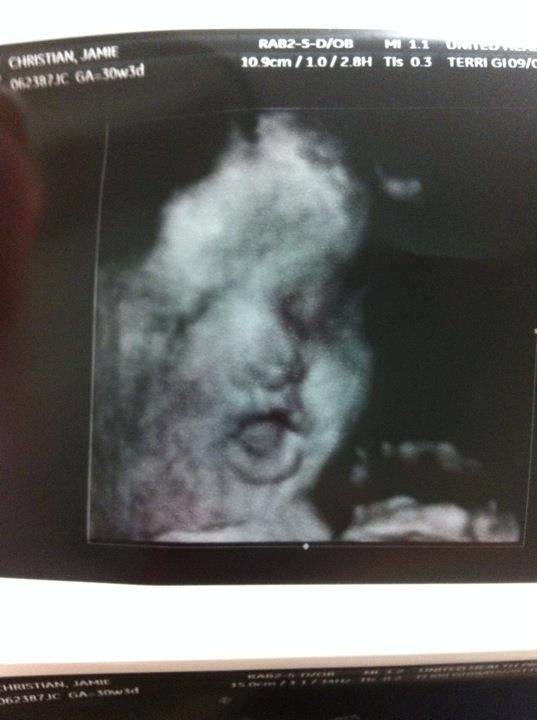

milestones: switched from monthly appointments to bi weekly appointments! at my 31 week appointment i had a growth ultrasound.. i'm baking a big boy! they estimated his weight to be 3lbs 14oz.. so they're expecting him to weigh between 7-8lbs at birth. tyler took a half-day so he could be at the ultrasound since we hadn't had one since our 18 week appointment. the tech gave us lots of great pictures in 3D.. it was so amazing to see him and features. we've decided he has tyler's nose and chin and my mouth.. and he has lots of hair :)

i couldn't gush about our 3D ultrasound and not share pictures of his precious face :)